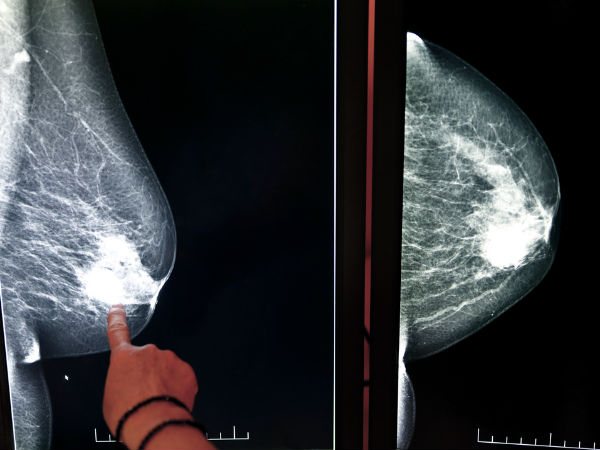

സ്തനങ്ങളിലെ ഈ മാറ്റങ്ങള് അവഗണിയ്ക്കരുത്

സ്തനാര്ബുദത്തെ കുറിച്ച് എല്ലാവരും ബോധവാന്മാരാണ്. എന്നാല് പല സ്ത്രീകള്ക്കും ഇതിന്റെ ലക്ഷണങ്ങളഎക്കുറിച്ച് കൃത്യമായ ധാരണ ഉണ്ടാവില്ല. ഇത് പലപ്പോഴും ഗുരുതരമായ അവസ്ഥയിലാണ് നമ്മളെ കൊണ്ടു ചെന്നെത്തിക്കുന്നത്.

ക്യാന്സര് പൂര്ണമായും നിങ്ങളെ കീഴടക്കിയതിനു ശേഷം മാത്രമാണ് പലരും ഇത് തിരിച്ചറിയുന്നത്. എന്നാല് ഇനി സ്തനാര്ബുദത്തെക്കുറിച്ച് നിങ്ങള്ക്ക് തന്നെ മനസ്സിലാക്കാം.

സ്തനങ്ങളില് വരുന്ന ചെറിയ മാറ്റങ്ങള് പോലും അവഗണിക്കാതെ കൃത്യമായി വിശകലനം ചെയ്താല് സ്തനാര്ബുദത്തില് നിന്നും രക്ഷ നേടാം.